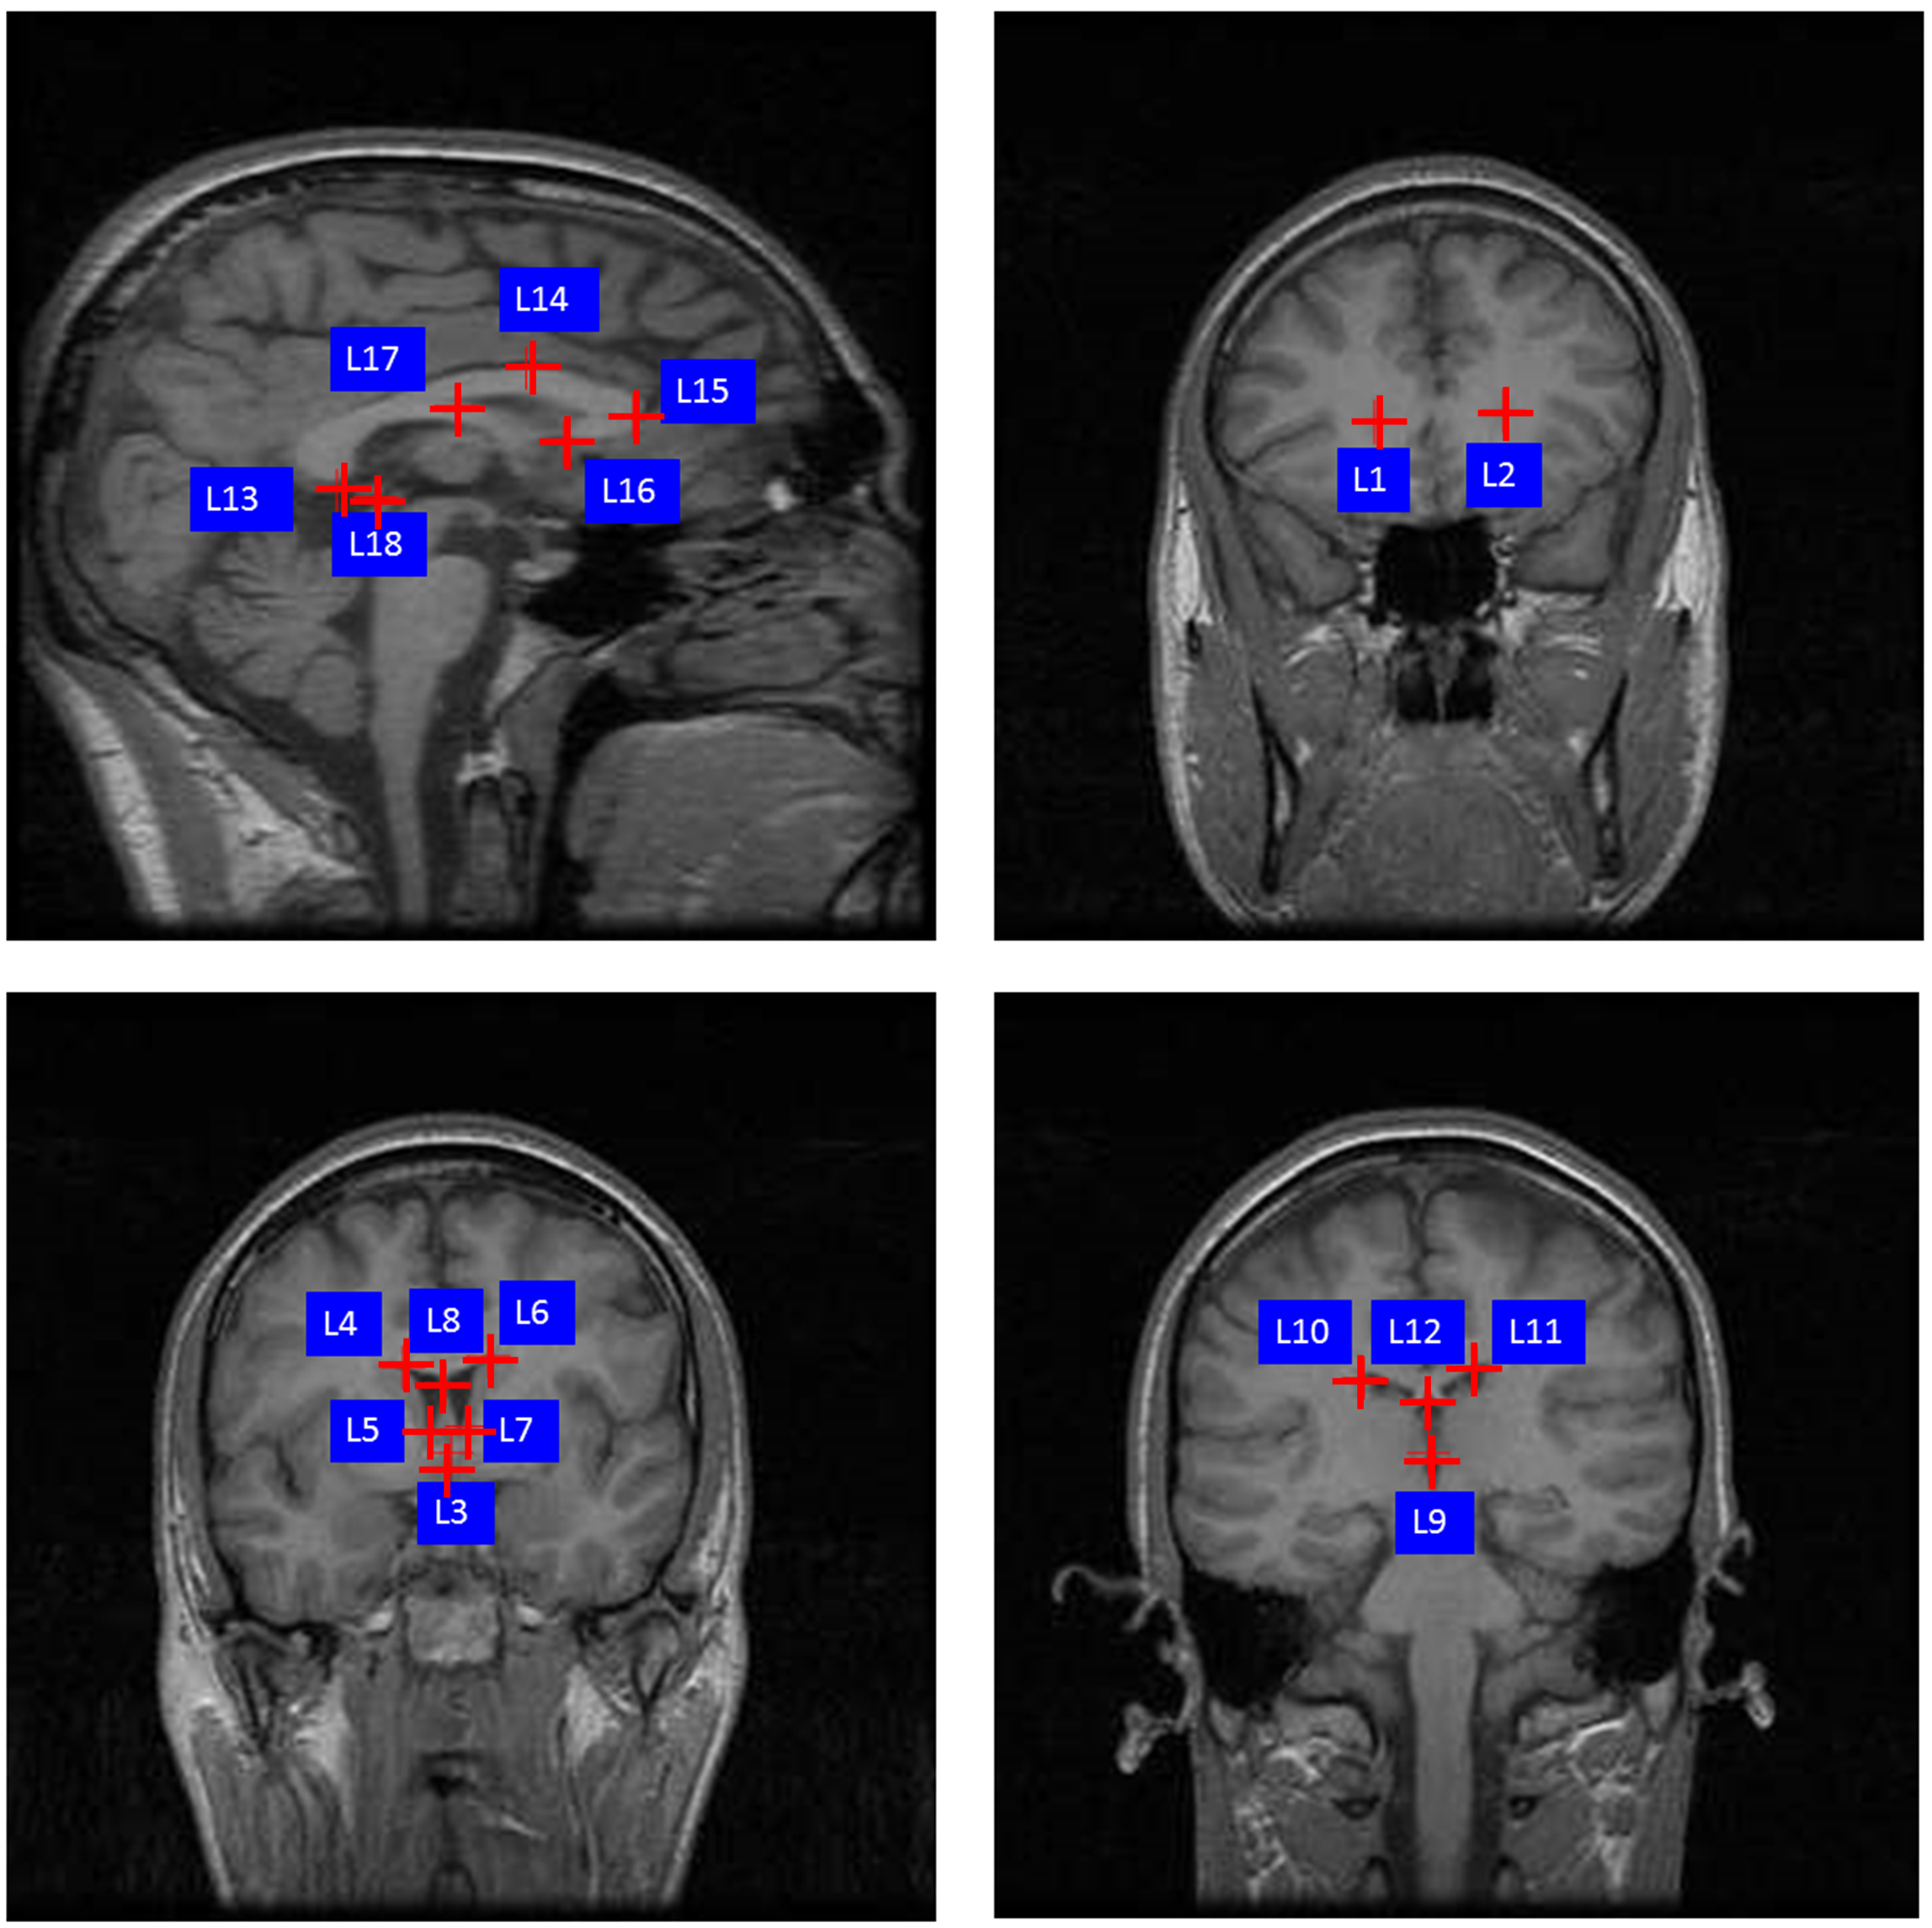

IV-E Experiments on MRI Brain Registration

The T1-weighted MRI brain data with ground-truth segmentation are selected from the LONI Probabilistic Brain Atlas (LPBA40) [44], which consists of images from 40 subjects. We discard twenty images with tilted head positions and select the remaining twenty subjects. This dataset provides ground-truth segmentation masks. Eighteen well-defined anatomic landmarks (see Figure 4) that are distributed mainly in the lateral ventricle and the median sagittal plane [45] are manually annotated by three doctors, and the average coordinates from three doctors are considered as the ground-truth positions of the landmarks. The original size of the 3D brain MRI volume is 256×\times124×\times256 voxels, which are zero-padded to 256×\times128×\times256 and resized to 256×\times256×\times256 voxels. Affine transformation (implemented by ANTs with mutual information as the metric) is applied to each 3D brain image before we slice 3D volume into 2D images. During the training phase, a pair of slicing planes A and B at the same position of the MRI volumes are interchangeably treated as a pair of fixed and moving images. This procedure produces a total of 291,840 (20×\times19×\times256×\times3, 20×\times19 subject pairs, 256 positions and 3 directions) 2D images for training and evaluation.

Refer to caption

Figure 4: This sketch illustrates the 18 landmarks selected in the brain dataset. L1: right lateral ventricle posterior, L2: left lateral ventricle posterior, L3: anterior commissure corresponds to the midpoint of decussation of the anterior commissure on the coronal AC plane, L4: right lateral ventricle superior, L5: right lateral ventricle inferior, L6: left lateral ventricle superior, L7: left lateral ventricle inferior, L8: middle of lateral ventricle, L9: posterior commissure corresponds to the midpoint of decussation, L10: right lateral ventricle superior, L11: left lateral ventricle superior, L12: middle of lateral ventricle, L13: corpus callosum inferior, L14: corpus callosum superior, L15: corpus callosum anterior, L16: corpus callosum posterior tip of genu corresponds to the location of the most posterior point of corpus callosum posterior tip of genu on the midsagittal planes, L17: corpus callosum fornix junction, L18: pineal body.

Additional MRI brain data is needed to improve the performance of our unsupervised methods. We randomly select 35 normal patients provided by ADNI [46] (Alzheimer’s Disease Neuroimaging Initiative) to enlarge our training set. The original size of additional MRI brain data is 196×\times256×\times256 voxels, which is rotated into 256×\times196×\times256 and resized into 256×\times256×\times256 voxels. Then, the additional MRI brain data is preprocessed in the same way as the data of the LONI Probabilistic Brain Atlas (LPBA40) [44].